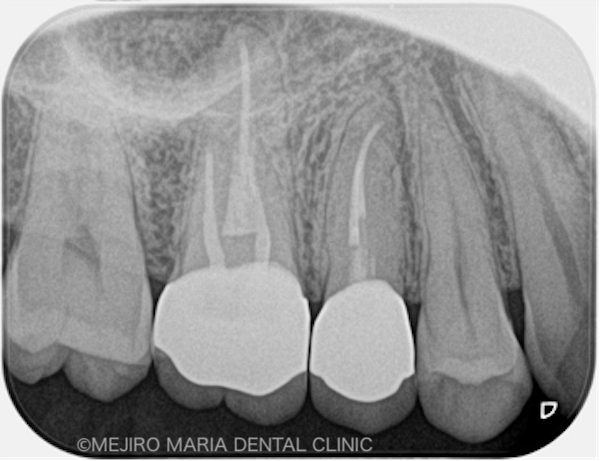

術後3ヶ月の経過は良好だったため、最終補綴処置を完了し、その後1年間、経過を確認しました。その結果、右上6番の歯に確認できていた病変も消失し、現時点は予後良好と判断しています。